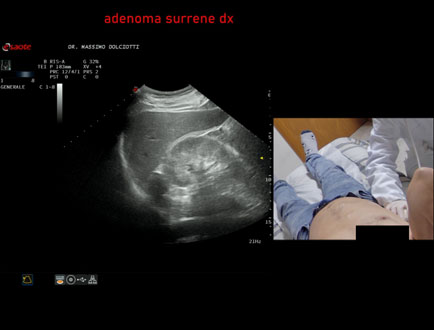

Data inserimento: 06/11/2025

Ecografia del: 31/10/2025

Strumento: Esaote MyLab Eight

Sonda: Convex Multifrequenza 1-8 MHz

Età Paziente: F 69 anni

Motivazione dell'esame: follow up per piccolo adenoma surrenalico.

Commento all'esame: le immagini ed il video documentano in sede surrenalica destra, formazione ipoecogena, a margini definiti, rotondeggiante, delle dimensioni di 15,8 x 14,8 mm, da ricondurre ad adenoma surrenalico.

Conclusioni: piccolo adenoma surrenalico destro (small right adrenal adenoma).

Presentazione: Dr. Massimo Dolciotti - Ancona

Elaborazione digitale: Andrea Dini - Ancona